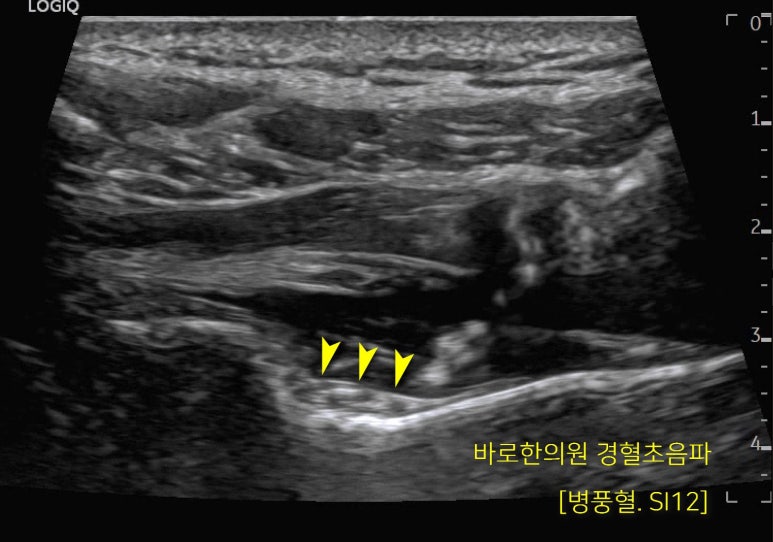

노란색 화살촉으로

표시한 부분이

바로 극상근을 지배하는

견갑상신경이 지나가는 곳입니다.

신경과 혈관의 위치를

초음파로 확인한 후

혈자리의 깊숙한 곳까지

안전하고 정확하게 시술해드렸습니다.